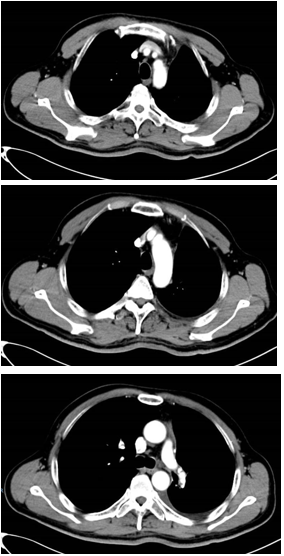

胸部CT显示左侧上叶支气管旁部发现一不规则、边界不清的软组织肿块,大小约为41mm×26mm。增强扫描后,肿瘤呈显著不均匀强化,与肿大的淋巴结粘连且难以区分,部分包裹左上叶支气管,导致管腔狭窄。左上叶肺叶间裂增厚,多个结节灶提示可能存在肺内转移。

治疗缓解评估:影像学(CT)显示原发肿瘤及叶间淋巴结明显缩小;支气管镜显示左上叶开口通畅,原肿块显著退缩,可见白色坏死组织;疗效评估为PR。

手术治疗:新辅助治疗完成后6周,行VATS辅助左上肺叶切除+肺门及纵隔淋巴结清扫;术中血管解剖清晰,淋巴结清扫顺利;切口小,胸腔镜辅助下完成重建。

术后病理结果:鳞状细胞癌;残留肿瘤细胞为5%;间质成分(纤维化/炎症)为90%;淋巴结为0/13转移;ypT1aN0M0,IA期;疗效评估为MPR。